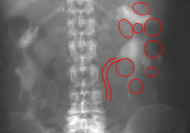

Ein i.v.-Pyelogramm kann im Rahmen der differentialdiagnostischen Abklärung des Flankenschmerzes indiziert sein (Abbildung). Sofern schon eine ausgeprägte Niereninsuffizienz vorliegt, sollte die Abklärung mit einem retrograden Pyelogramm erfolgen (Abbildung 5).